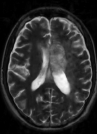

Table 2 shows the SNR values of the different reconstruction results. Figure 5 shows the reconstruction results at 5,10 and 16.6-fold acceleration of a patient with OPG. Both TCS-MRI and LACS-MRI exhibit almost no loss of information at 10-fold acceleration. Similar results are obtained with CS-MRI only at 5-fold acceleration.

This experiment shows that thanks to the ability to under-sample the 2D phase encode plane, the advantage of temporal similarity exploitation is emphasized. Therefore, LACS-MRI allows shortening the scanning time by a factor of 10, with no significant loss of information in this case.